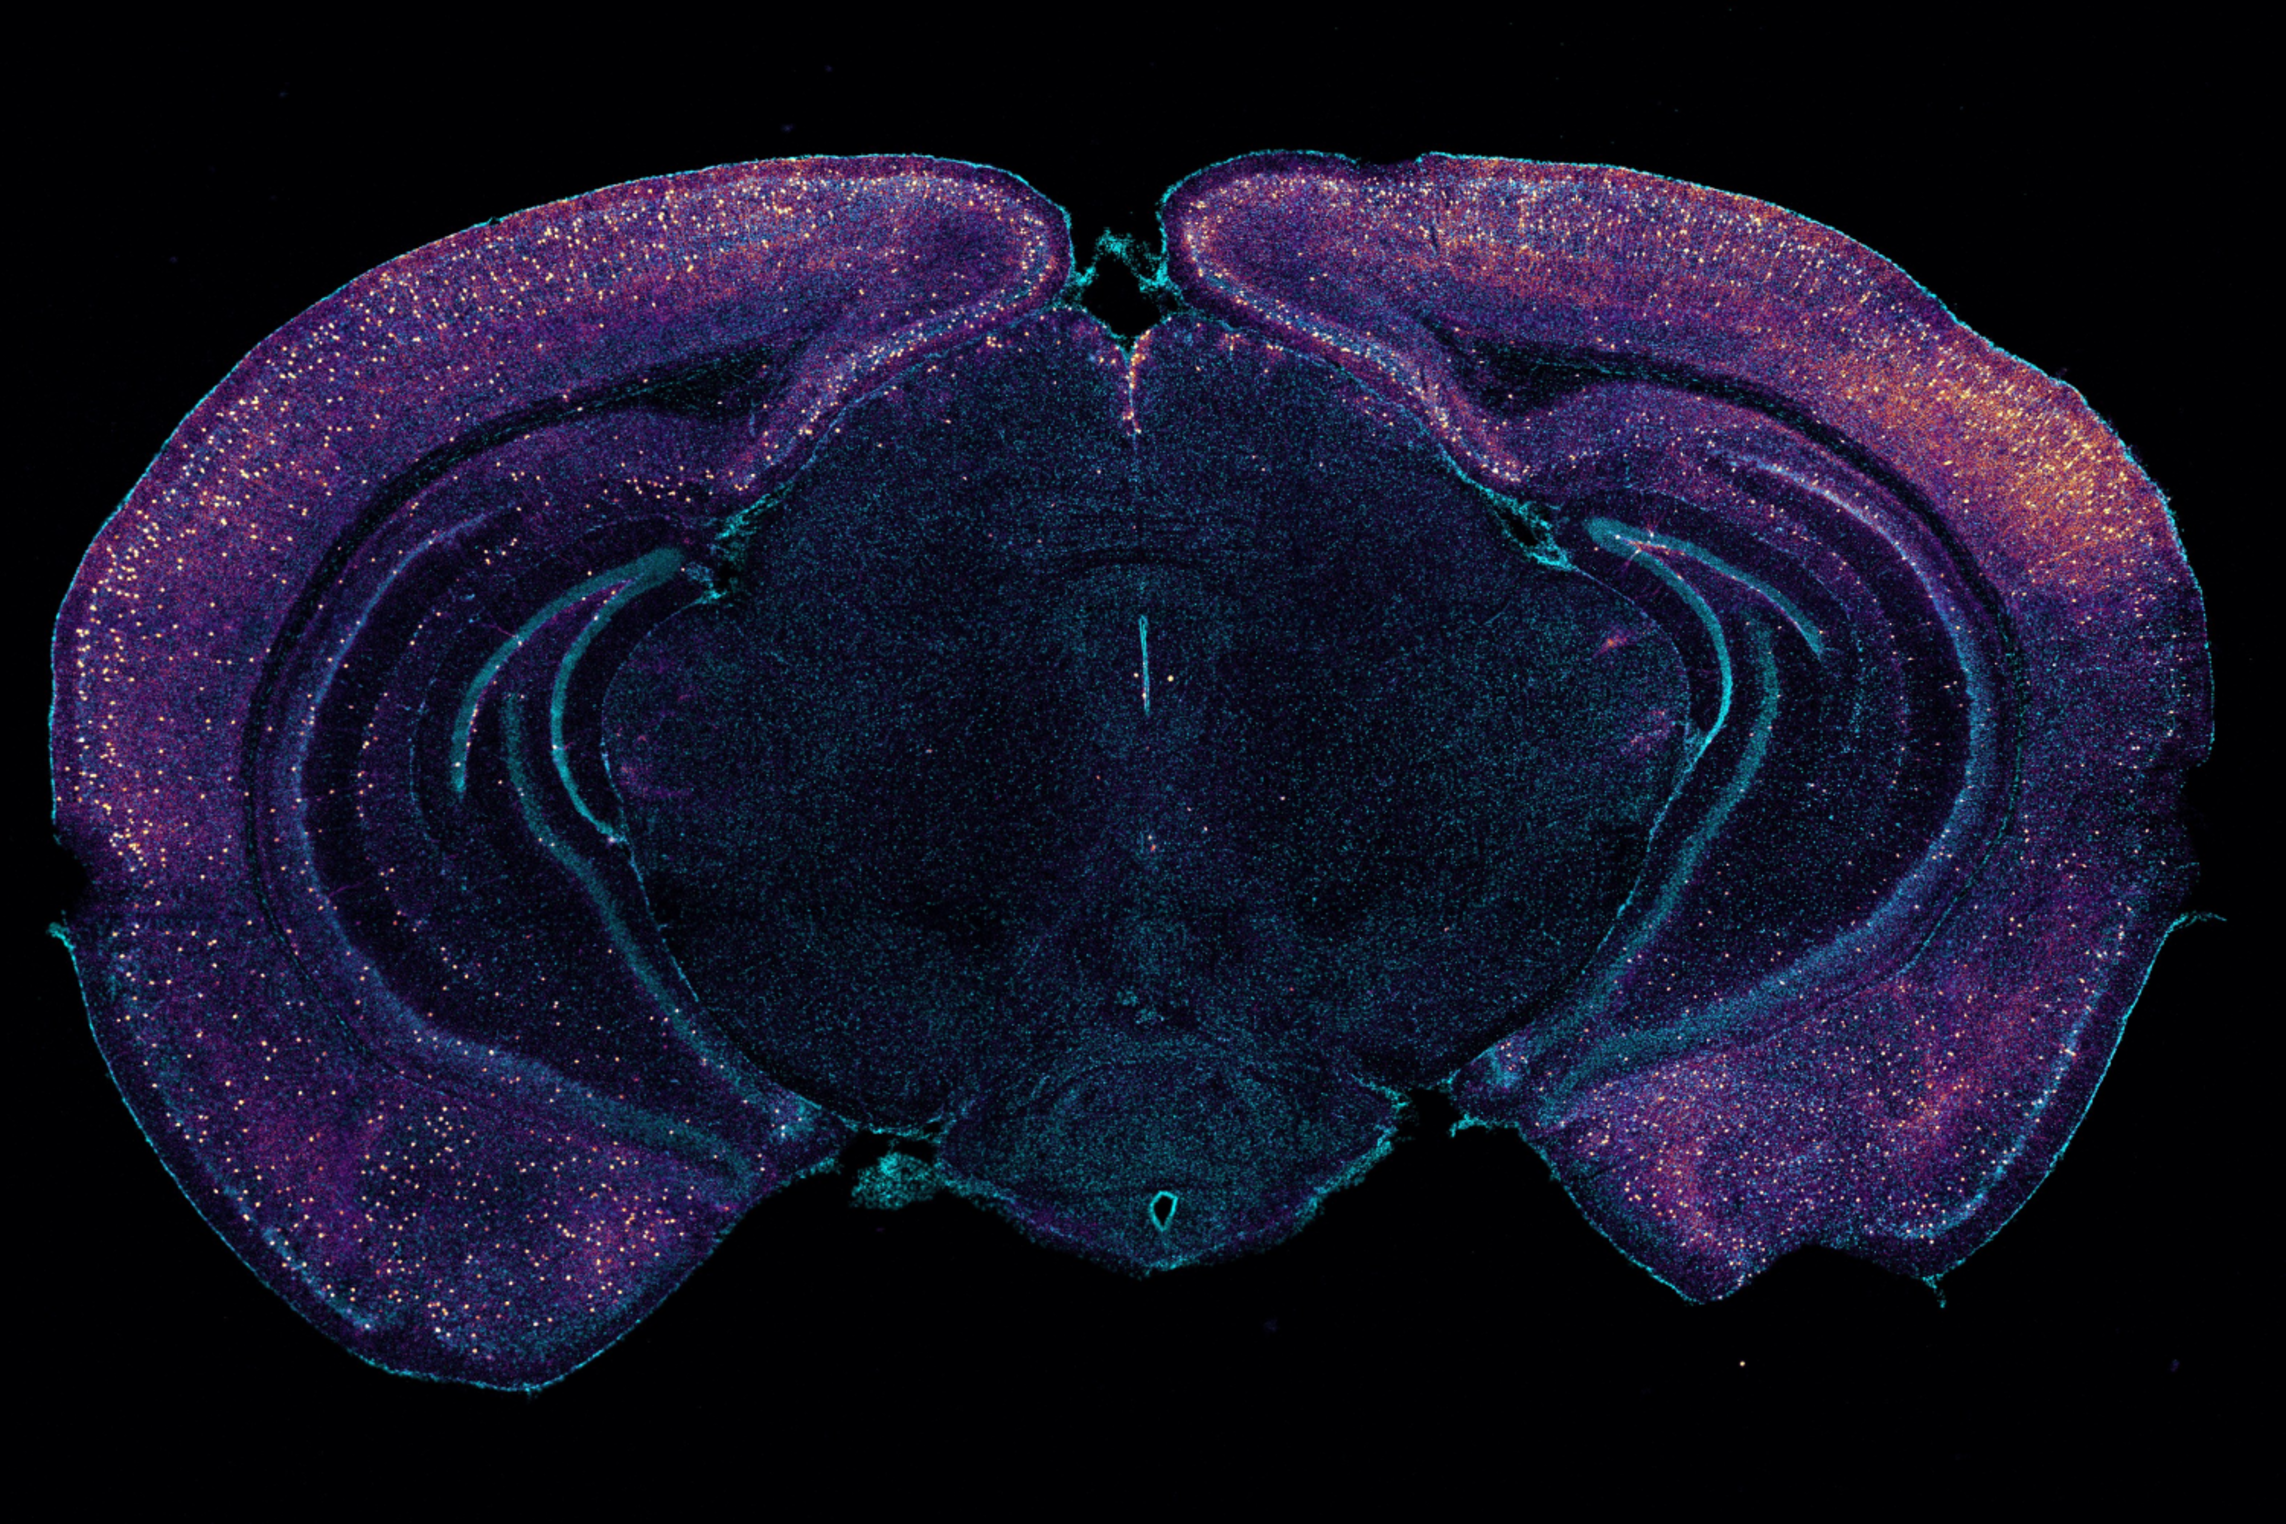

Working with “5XFAD” mice, which genentically model Alzheimer’s, Murdock and co-authors first replicated the lab’s prior results that 40Hz sensory stimulation increases 40Hz neuronal activity in the brain and reduces amyloid levels. Then they set out to measure whether there was any correlated change in the fluids that flow through the glymphatic system to carry away wastes. Indeed, they measured increases in cerebrospinal fluid in the brain tissue of mice treated with sensory gamma stimulation compared to untreated controls. They also measured an increase in the rate of interstitial fluid leaving the brain. Moreover, in the gamma-treated mice he measured increased diameter of the lymphatic vessels that drain away the fluids and measured increased accumulation of amyloid in cervical lymph nodes, which is the drainage site for that flow.